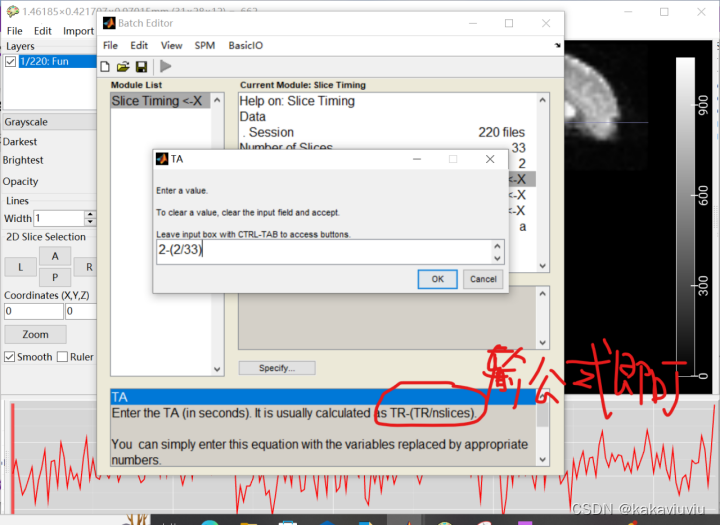

TA:一次全脑扫描中,最后一层与第一层的时间间隔;

TA=TR-(TR/扫描层数)

填写TA